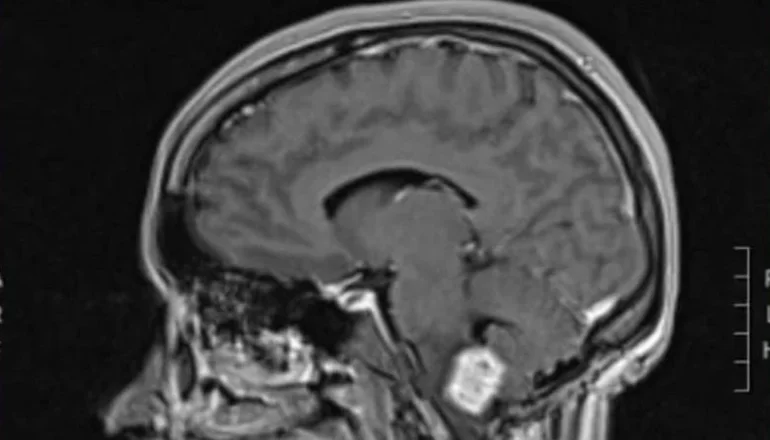

En el 2022, empezó de nuevo con dolores de cabeza, malestar e inestabilidad. Se hizo una resonancia y le descubrieron la lesión que tiene actualmente en la médula, que es la misma que le operaron en el 2016.

Es así que viajó a Córdoba en busca de otro punto de vista médico. Allí le hicieron una resonancia y le detectaron tres tumores, dos en el cerebelo y uno a nivel medular. La indujeron a un coma para descomprimir todo, pudieron sacar los tumores del cerebelo pero quedó esta lesión en la médula con la especulación de que no crezca y con la posibilidad de acceder a la medicación.